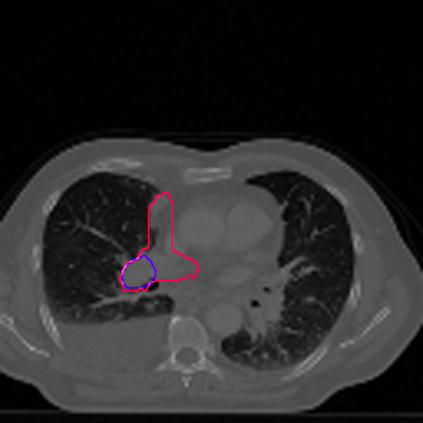

Lung cancer is a leading cause of death in most countries of the world. Since prompt diagnosis of tumors can allow oncologists to discern their nature, type and the mode of treatment, tumor detection and segmentation from CT Scan images is a crucial field of study worldwide. This paper approaches lung tumor segmentation by applying two-dimensional discrete wavelet transform (DWT) on the LOTUS dataset for more meticulous texture analysis whilst integrating information from neighboring CT slices before feeding them to a Deeply Supervised MultiResUNet model. Variations in learning rates, decay and optimization algorithms while training the network have led to different dice co-efficients, the detailed statistics of which have been included in this paper. We also discuss the challenges in this dataset and how we opted to overcome them. In essence, this study aims to maximize the success rate of predicting tumor regions from two dimensional CT Scan slices by experimenting with a number of adequate networks, resulting in a dice co-efficient of 0.8472.